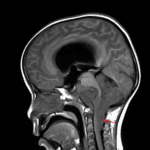

MRI

- Large, heterogeneously enhancing mass arising at the floor of the fourth ventricle and extending through the right greater than left foramina of Luschka and foramen of Magendie into the prepontine and premedullary cisterns and upper cervical spinal canal

- Extensive corresponding mass effect on the cerebellum, pons, medulla, and upper cervical spinal cord